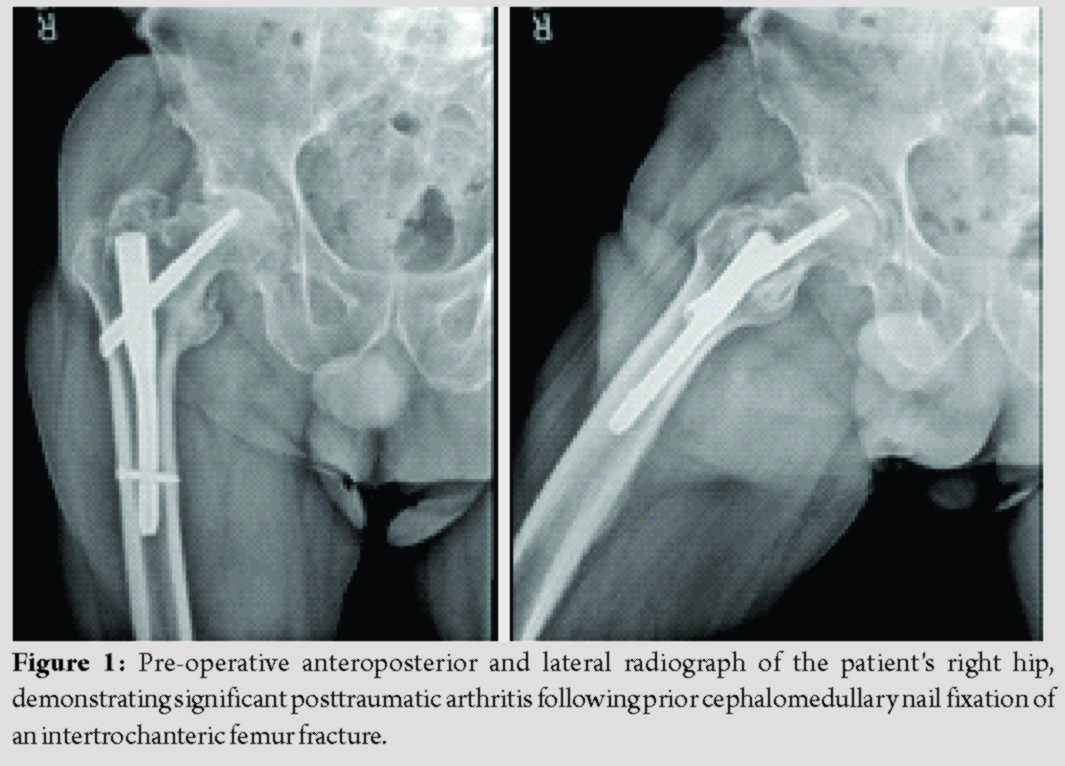

A 71-year-old man with a history of FXI deficiency presented to the orthopedic clinic with complaints of progressively worsening pain in his right hip. Of note, the patient had previously undergone cephalomedullary nail fixation of a right proximal femur fracture 3 years prior by another local orthopedic surgeon. The patient subsequently went onto heal this fracture; however, he did develop severe degenerative changes in his right hip along with significant post-traumatic arthritis (Fig. 1). Surgical options along with their risks and benefits were reviewed with the patient who ultimately elected to undergo conversion THA. Of note, the patient had a history of significant post-operative bleeding following a right-sided hernia repair done 19 years prior. At that time, his FXI deficiency was treated with only a single dose of fresh frozen plasma (FFP). Since then, he had undergone cephalomedullary nail fixation of both his left and right hips 3 and 5 years prior, respectively. He did not experience any post-operative bleeding or thromboembolic complications following either hip fracture surgery. The patient’s hematologist devised the following perioperative management strategy before his first hip fracture surgery: Preoperatively, a 5-g IV bolus of aminocaproic acid would be administered followed by aminocaproic acid as continuous venous infusion of 5 g in a 250 mL solution at 50 mL/h throughout the perioperative period. Postoperatively, tranexamic acid (TXA) would be administered as a 1 g bolus followed by 1 g every 8 h for 72 h for a total of nine doses. The patient would then be discharged on oral TXA at 1300 mg every 8 h for the first 7 days, with the frequency decreased to every 12 h for the subsequent week. He would also be administered subcutaneous enoxaparin 40 mg daily for venous thromboembolism prophylaxis.

Before conversion THA surgery, the patient was seen in the hematology clinic so that his perioperative plan could be reviewed before this surgery. The patient had been previously seen in this clinic at the time of this right hip fracture. At that time, the patient’s FXI deficiency was confirmed, with his factor XI assay at 1.9%, well below the normal value of 50–150% activity. Given the patient’s success with the aforementioned hematologic plan, it was agreed that the same protocol would be used for his THA conversion surgery. The patient was taken to the operating room for removal of the cephalomedullary nail and subsequent conversion to a THA. Pre-operative hemoglobin and hematocrit were 12.4 g/dL and 35.6%, respectively. Using the previous surgical incision, removal of the cephalomedullary nail was completed with some difficulty as the distal locking screw was stripped at the time of removal. Once this was completed, attention was turned to completing the THA. Utilizing a standard anterior approach, the proximal femur was cut in appropriate position, the acetabulum was reamed up to a size 57, and a size 58 cup was press-fit with excellent purchase. The cup was fixed with two screws into the ilium. Next, the femur was prepared. An 8″, size 18 Solution (Depuy, Warsaw Indiana) stem with a 36 + 5 head was deemed to provide adequate stability, and the final components were implanted. Blood loss was estimated at 700 mL. The patient was made toe-touch weight-bearing to the right lower extremity. There were no intraoperative complications experienced.